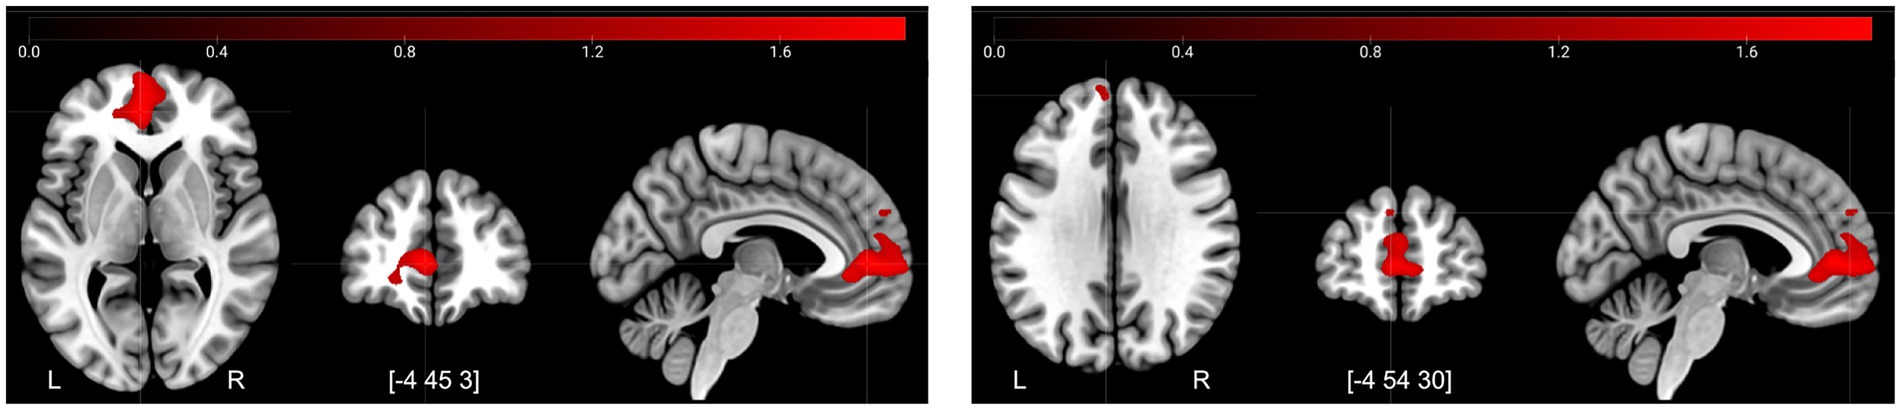

| Paracingulate gyrus | −4 | 45 | 3 | 2,399 | 1772 |

| Superior medial frontal gyrus | −4 | 54 | 30 | 40 | 1,267 |

| Superior frontal gyrus | 18 | 50 | 34 | 10 | 1,262 |

The decreases in activity after the control period for Retrieval–Control (Figure 4) corresponded mainly to a frontal-posterior cognitive control network (middle frontal gyrus, superior parietal lobe), visual association areas (cuneus/precuneus), motor areas (dorsal premotor region, presupplementary motor areas), and regions involved in memory retrieval—particularly during recognition tasks (anterior insula/posterior inferior frontal gyrus) (Buckner et al., 1996; Caviezel et al., 2020). In conjunction, these decreases suggest more efficient task-related information processing overall during the second session.

Figure 4

![MRI brain scans showing two sets of cross-sectional images highlighting regions of activation in red. Both sets display displays axial, coronal, and sagittal views, with intensity bars in shades of red at the top signifying activation levels. The markings L and R indicate left and right sides, and coordinates [-4 45 3] and [-4 54 30] specify slice positions.](https://www.frontiersin.org/files/Articles/1679873/xml-images/fnagi-17-1679873-g004.webp)

Decreases in activity at T2 compared to T1 for the contrast retrieval–control. Illustrated regions were significant at a TFCE FWE-corrected threshold of p < 0.05.

The increases in activity after the control period for Retrieval–Control (Figure 5), were found mainly in the pre-genual anterior cingulate cortex extending into the ventromedial PFC. In addition, there was a small cluster of increased activity in the dorsomedial PFC. These are areas associated with increased affective self-regulation (e.g., regulation of stress response) (Kerr et al., 2012).